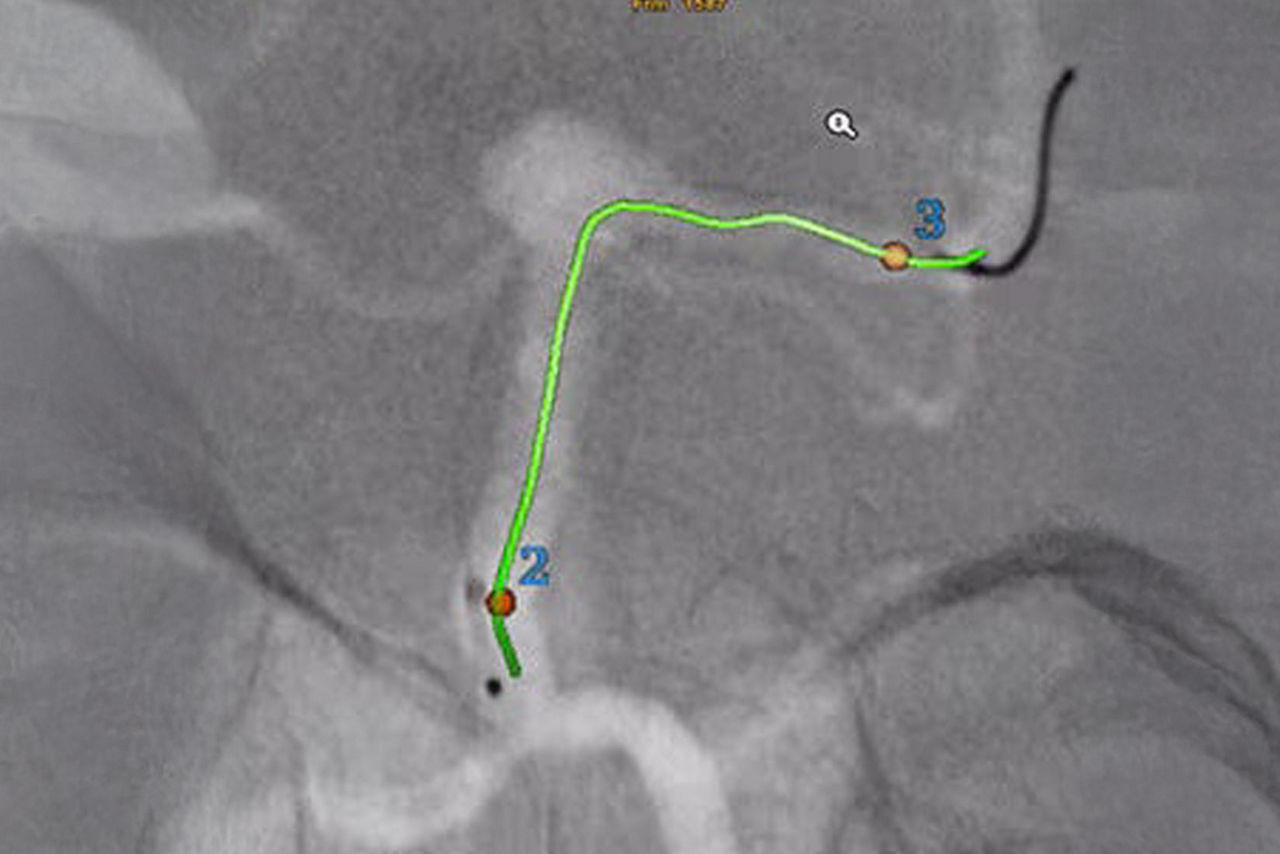

Guide

Select from the sub-volumes of vessels, centerlines, calcifications and landmarks to overlay on live fluoroscopy for 3D fusion guidance, with digital zoom, to guide recanalization.

Guide

Import segmented anatomy, centerline and landmarks and overlay them on live fluoroscopy on the frontal or lateral plane for 3D fusion guidance.